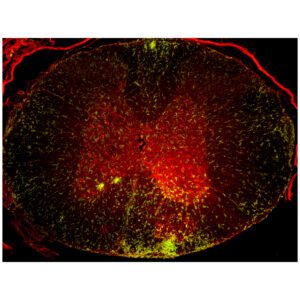

Neuroregeneration

Research aimed at promoting the regrowth and repair of nervous system tissues. This includes the generation of new neuronal cells as well as promoting axon regrowth and remyelination of damaged neurons.